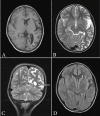

Rasmussen encephalitis is an extremely rare chronic inflammatory neurodegenerative disease affecting a single cerebral hemisphere, causing progressive neurological deterioration and intractable seizures. Imaging plays an important role in diagnosis by demonstrating focal or unihemispheric involvement and excluding other possible causes. Here, we report a case of Rasmussen encephalitis with an update on recent diagnostic criteria and emphasis on differential diagnoses which can be excluded on imaging.